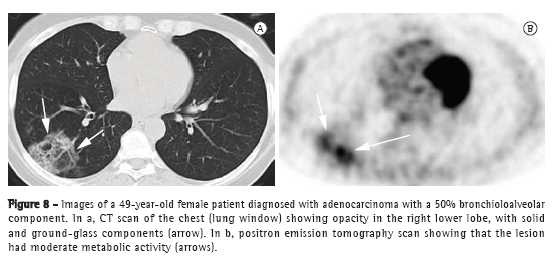

In the assessment of parenchymal consolidations suspected of malignancy, PET can be useful (Figure 8) for the characterization of the lesion or for the staging of neoplastic consolidations. However, it should be emphasized that 18F-FDG-labeled glucose uptake might be absent in some cases of BAC or adenocarcinoma with a bronchioloalveolar component (false negatives), and that PET can show false-positive results in inflammatory or infectious processes (or both).(5)